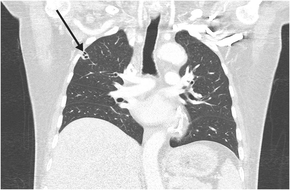

His clinical course was complicated by septic thromboembolism, including left renal vein thrombosis, multi‐territorial subcortical strokes, and disseminated lung infection, with multiple peripheral cavitating nodules (Box 3). Transoesophageal echocardiogram and cardiac magnetic resonance imaging showed no evidence of infective endocarditis or patent foramen ovale.